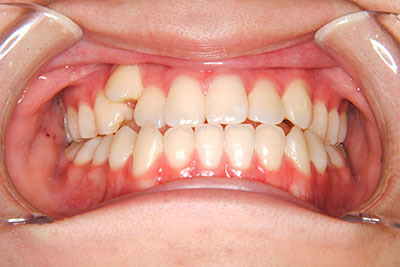

小学生高学年や中高生で矯正治療を考えている方へ

歯が乳歯から永久歯に生え変わった小学生高学年や、中高生でも矯正治療に手遅れということは全くありません。

成長中の顎の骨を矯正できたり、この時期の矯正はおとなになってから矯正治療を始めるよりも短期間で済むことがほとんどです。当院だとおおよそ1年で動的治療(マルチブラケット装置をつける期間)が終わることが多いです。